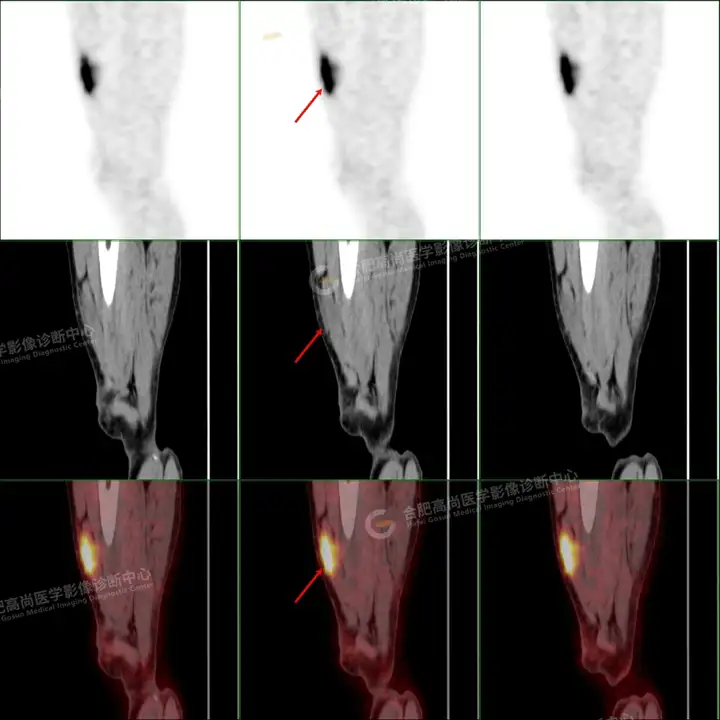

PETCT检查所示:图1、3-17全身多处(双上臂、胸背部、左侧乳腺、左侧腰部、腹壁、双侧臀部及双侧大腿)皮肤下结节及肿块样软组织密度灶,FDG代谢不同程度增高,双侧颈部、左侧锁骨区、纵隔内(1区)及双侧腋窝多发肿大淋巴结,FDG代谢明显增高,符合皮肤来源淋巴瘤。

图2右侧颈部包块切除术后,右侧锁骨区术区皮下片状密度增高灶,FDG代谢异常增高,考虑术后炎性反应。